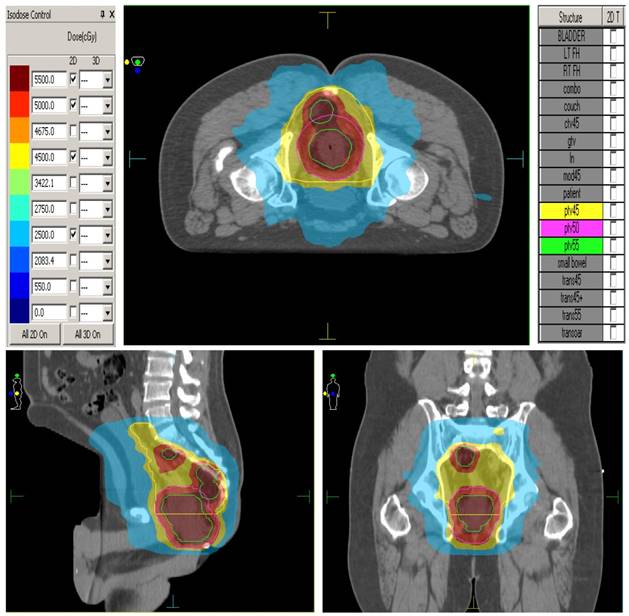

The elective CTVs are generated in accordance to the RTOG anorectal contouring guidelines (https://www.rtog.org/CoreLab/ContouringAtlases/Anorectal.aspx). The GTV-P (Primary) is the rectal tumour seen on CT/MRI scans. The GTV-N is the grossly enlarged lymph nodes seen on CT/MRI. The CTV-P (primary) is the GTV-P plus 2 cm margin, ensuring to extend to the entire mesorectum and presacral region at involved levels. The CTV-N is the GTV-N plus a 5mm margin. Presacral lymphatic CTV is generated by contouring from mid S1-S5 and 8 mm tissue anterior to the anterior border of the sacral bone. The mesorectum and perirectal lymphatics CTV is generated by utilizing the following anatomic landmarks: Posterior Border: anterior border of the sacrum and gluteus maximus, Lateral Border: ileum, piriformis and obturator muscles, Anterior Border: should overlap by 1 cm into the bladder, vagina or prostate. The PTV45 is generated by expanding all of the above structures by 0.5 cm symmetrically and unifying them into one 3-dimensional volume for planning purposes. PTV 50 is the CTV-P plus a 5mm margin. PTV 55 includes GTV-P plus 1 cm margin and CTV-N plus 5mm margin. Megavoltage cone beam CT scans are performed daily prior to treatment for treatment verification. Figure 1. shows the ability of IMRT to conform radiation doses and 'dose paint' to target volumes.

Figure 1

Dose painting with IMRT

Treatment plans for patients will consist of a single phase using a synchronous integrated boost technique (SIB): Inverse-planned IMRT- will deliver to PTV 45 a total dose of 45 Gy in 1.8 Gy daily fractions, to PTV 50 a total dose of 50 Gy in 2 Gy daily fractions and to PTV 55 a total dose of 55 Gy in 2.2 Gy daily fractions. Patients will receive treatment 5 days per week, in once daily fractions, over 5 weeks duration. Dose is prescribed according to ICRU 83. Dose constraints to organs at risk are as follows: Small bowel - no more than 180 cc above 3 5 Gy, no more than 100 cc above 40 Gy, no more than 65 cc above 45 Gy, no small bowel volume should receive 50 Gy. Femoral heads- no more than 40% volume above 40Gy. no more than 25% above 45 Gy, no femoral head volume should receive 50Gy. Bladder- no more than 40% volume above 40 Gy, no more than 15% above 45 Gy, no bladder volume should receive 50 Gy.